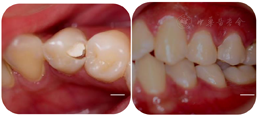

34远中邻牙合面可见白色暂封材料,部分脱落松动,叩痛(±),不松动,牙龈龈缘稍红肿,无窦道口,牙髓活力测试:无反应,咬合:无异常动度。见图1。根尖片示:34牙冠远中邻合面高密度充填影像达髓腔;髓腔高大,髓室底低,根分叉向根方移位,牙根中下1/3膨大,根管影像不清,根周膜影像不清。见图2A。CBCT示:⑴横断面:髓腔高大,髓室底低,牙根下段根管形态复杂,中下1/3牙根横截面呈C形(见图3A、3B);⑵近远中观:颊侧通路影像清晰,舌侧通路影像不清,髓室底距颊尖约:14.0mm,髓室底距CEJ约:7.6mm(见图3C、3D),测量牛牙症指数(taurodontic index,TI),AB:15mm、AC:7.6mm,AB / AC x100%= 50.7%,为重度牛牙症(见图5);⑶颊舌侧观:舌侧通路弯曲明显,呈"S"形,根尖1/3根管影像不清(见图3E)。

34远中邻合面可见白色暂封材料,部分脱落松动,叩痛(±),不松动,牙龈龈缘稍红肿,无窦道口,牙髓活力测试:无反应,咬合:无异常动度。术前行完善的根尖片和锥形束CT(cone beam computed tomography,CBCT)检查。